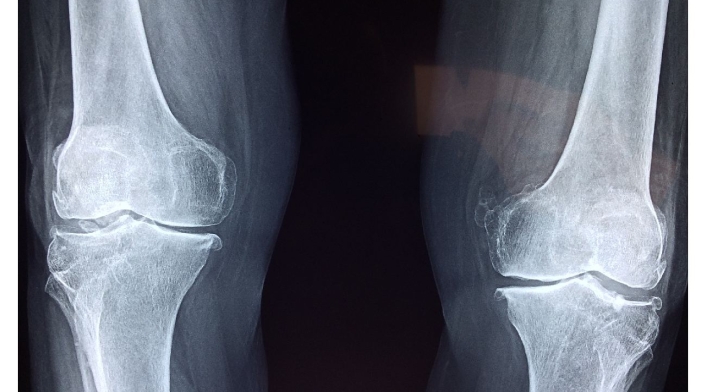

Según la Organización Mundial de la Salud la osteoporosis es una enfermedad que se caracteriza por la disminución de masa ósea, causando un incremento en la fragilidad y debilidad del hueso, las personas que la padecen son más susceptibles a sufrir algún tipo de fractura. La gran mayoría de personas alcanza una densidad ósea alrededor de los 30 años, luego de esta edad la renovación continúa, pero de una manera menor.

Los tres tipos de osteoporosis más comunes son: Osteoporosis postmenopáusica, la cual se presenta en mujeres mayores de 45 años y sucede por la falta de estrógenos que deja de producir la mujer; Osteoporosis senil, esta es la más común y se da por la pérdida de masa ósea a causa de la edad y, por último, la Osteoporosis corticoidea que se da por el consumo de algunos medicamentos y es inducida por glucocorticoides (compuesto que pertenece al tipo de los llamados esteroides).

- Las fracturas más frecuentes causadas por osteoporosis son en la columna, caderas y muñecas: Esto debido al tipo de hueso que está en estas zonas, pues es un hueso más frágil, así mismo se cree que las personas de la tercera edad suelen caerse de lado sobre la cadera.

- La densidad mineral ósea disminuye después de los 30 años: Esto se da en las mujeres, los hombres están más protegidos por algunos factores como: la perdida de hueso se da más tarde que en las mujeres, los hombres alcanzan en el crecimiento un pico de masa mayor que las mujeres, por otra parte, la disminución de hormonas masculinas (andrógenos) se da más lenta.